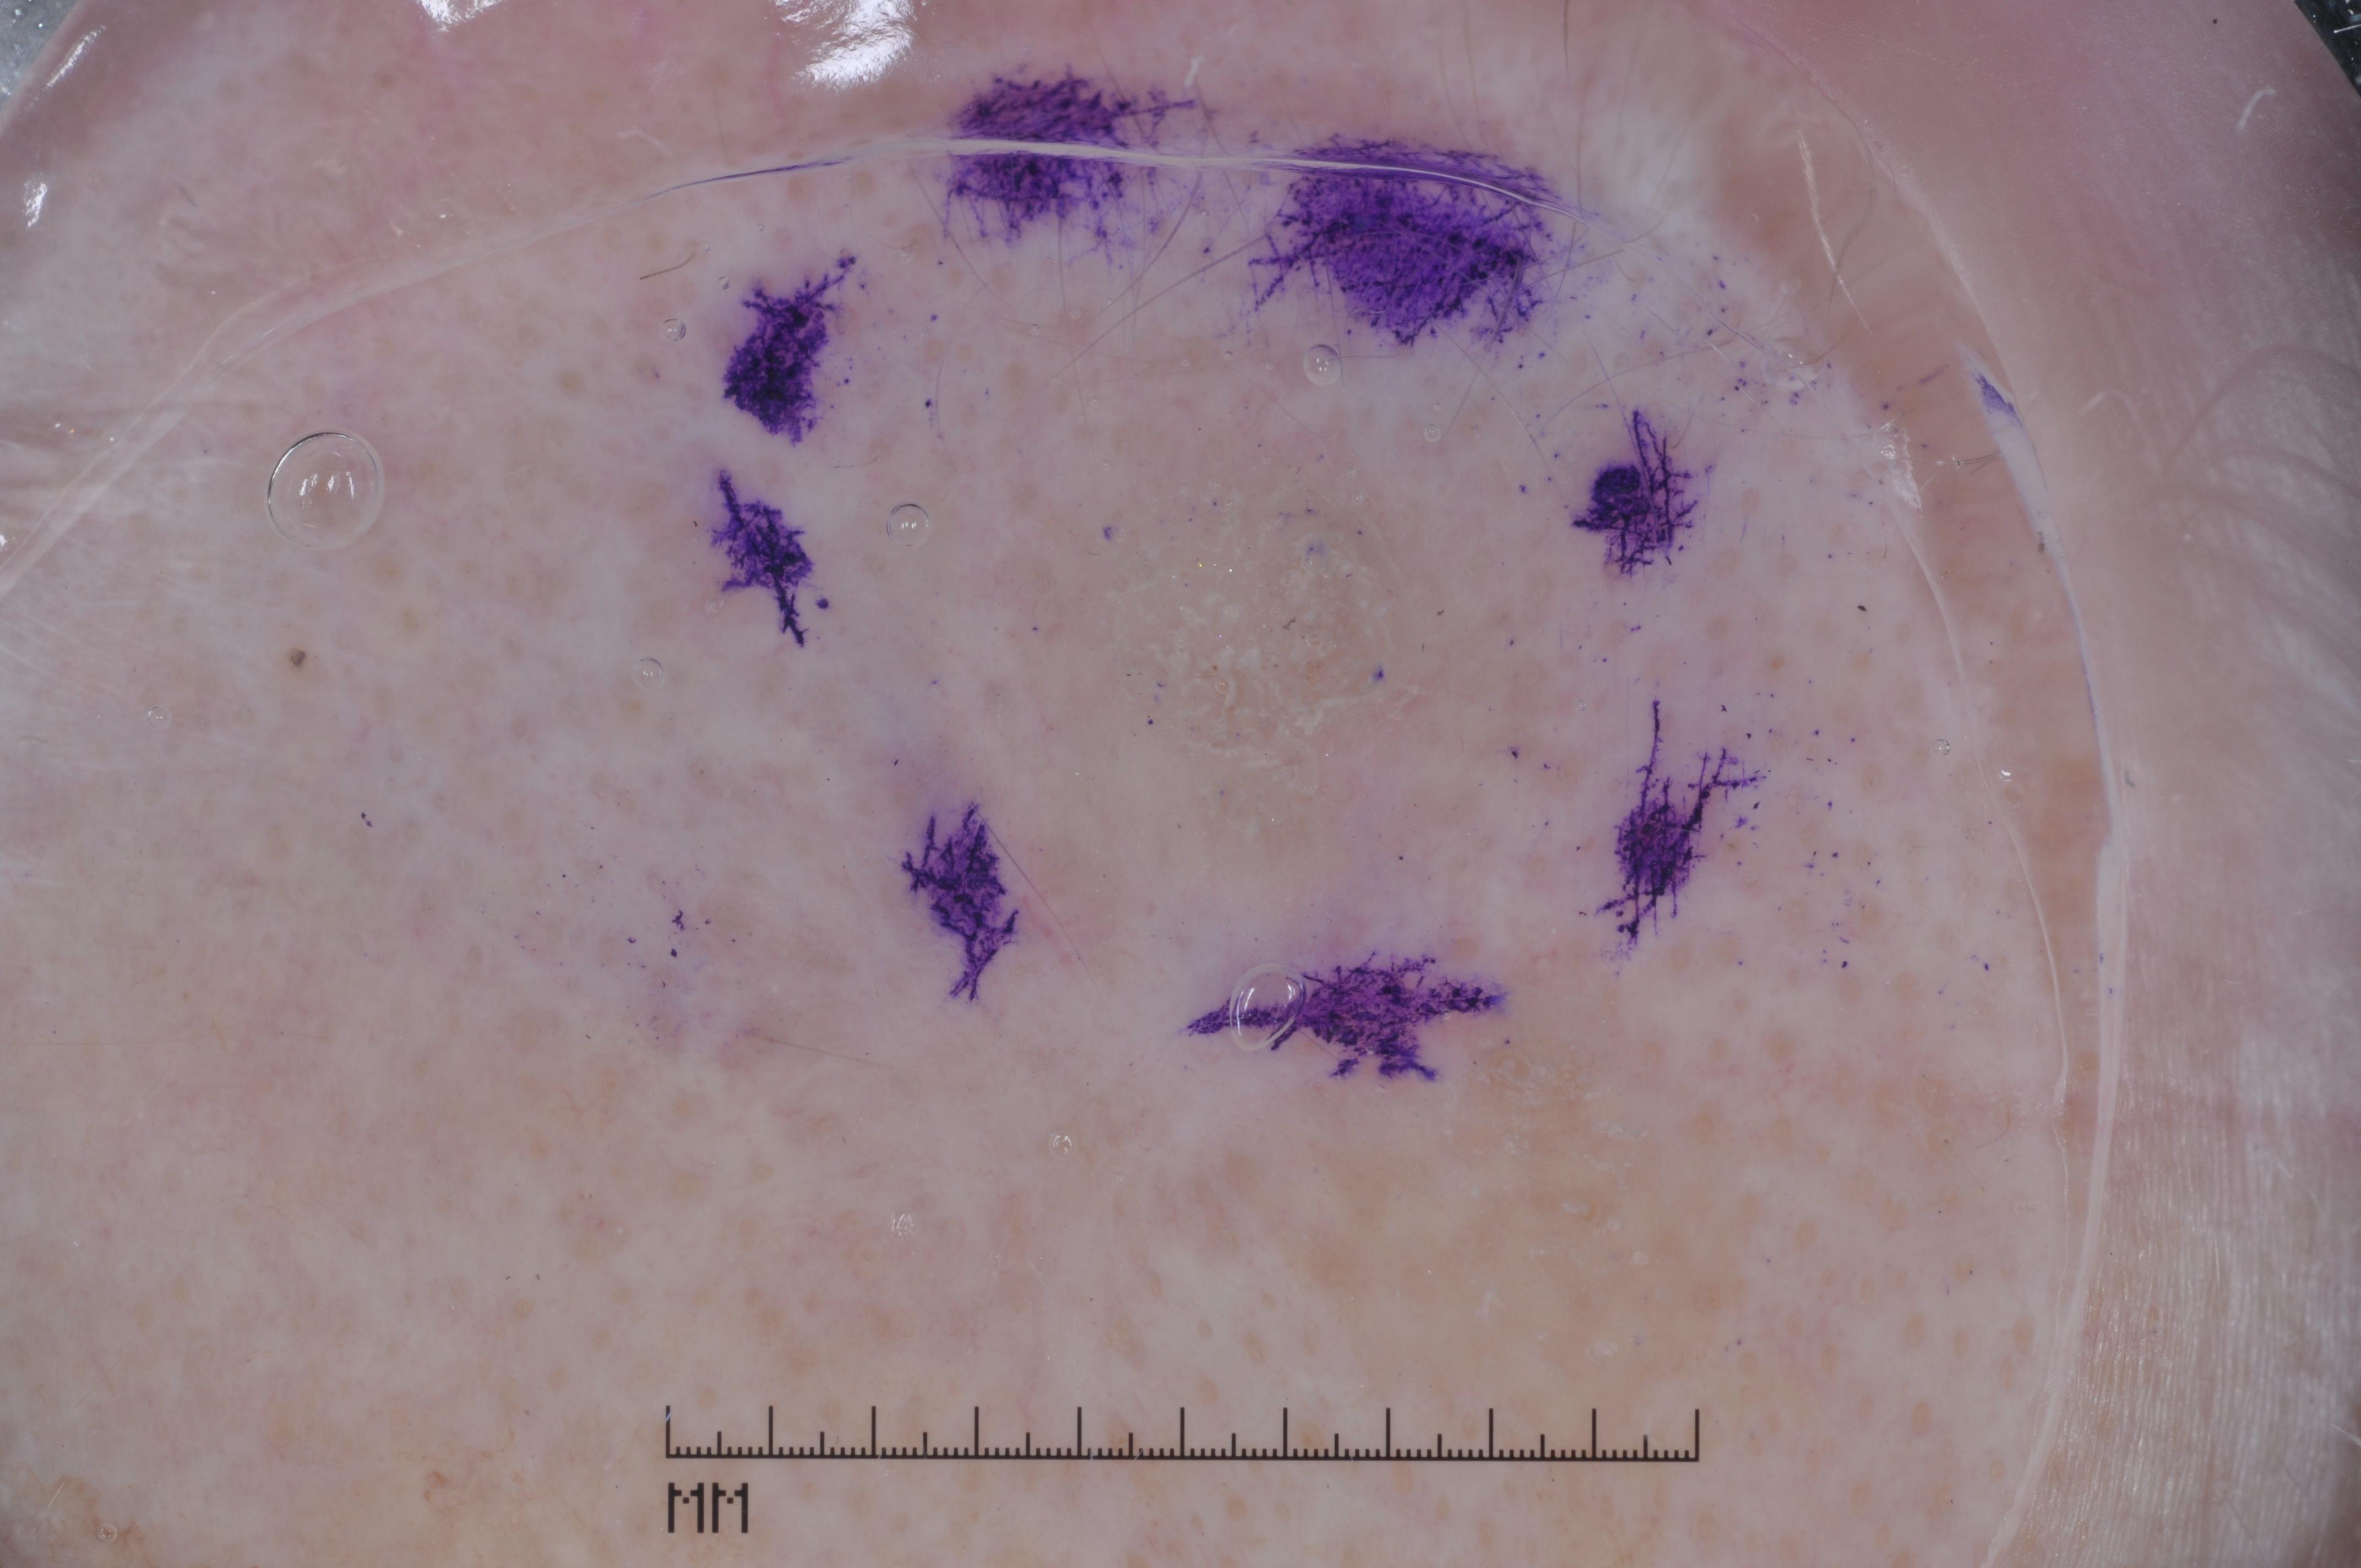

{

"age_approx": 70,

"anatom_site_general": "posterior torso",

"concomitant_biopsy": true,

"dermoscopic_type": "contact non-polarized",

"diagnosis_1": "Benign",

"diagnosis_2": "Benign melanocytic proliferations",

"diagnosis_3": "Nevus",

"diagnosis_confirm_type": "histopathology",

"image_type": "dermoscopic",

"lesion_id": "IL_2525413",

"melanocytic": true,

"sex": "male"

}